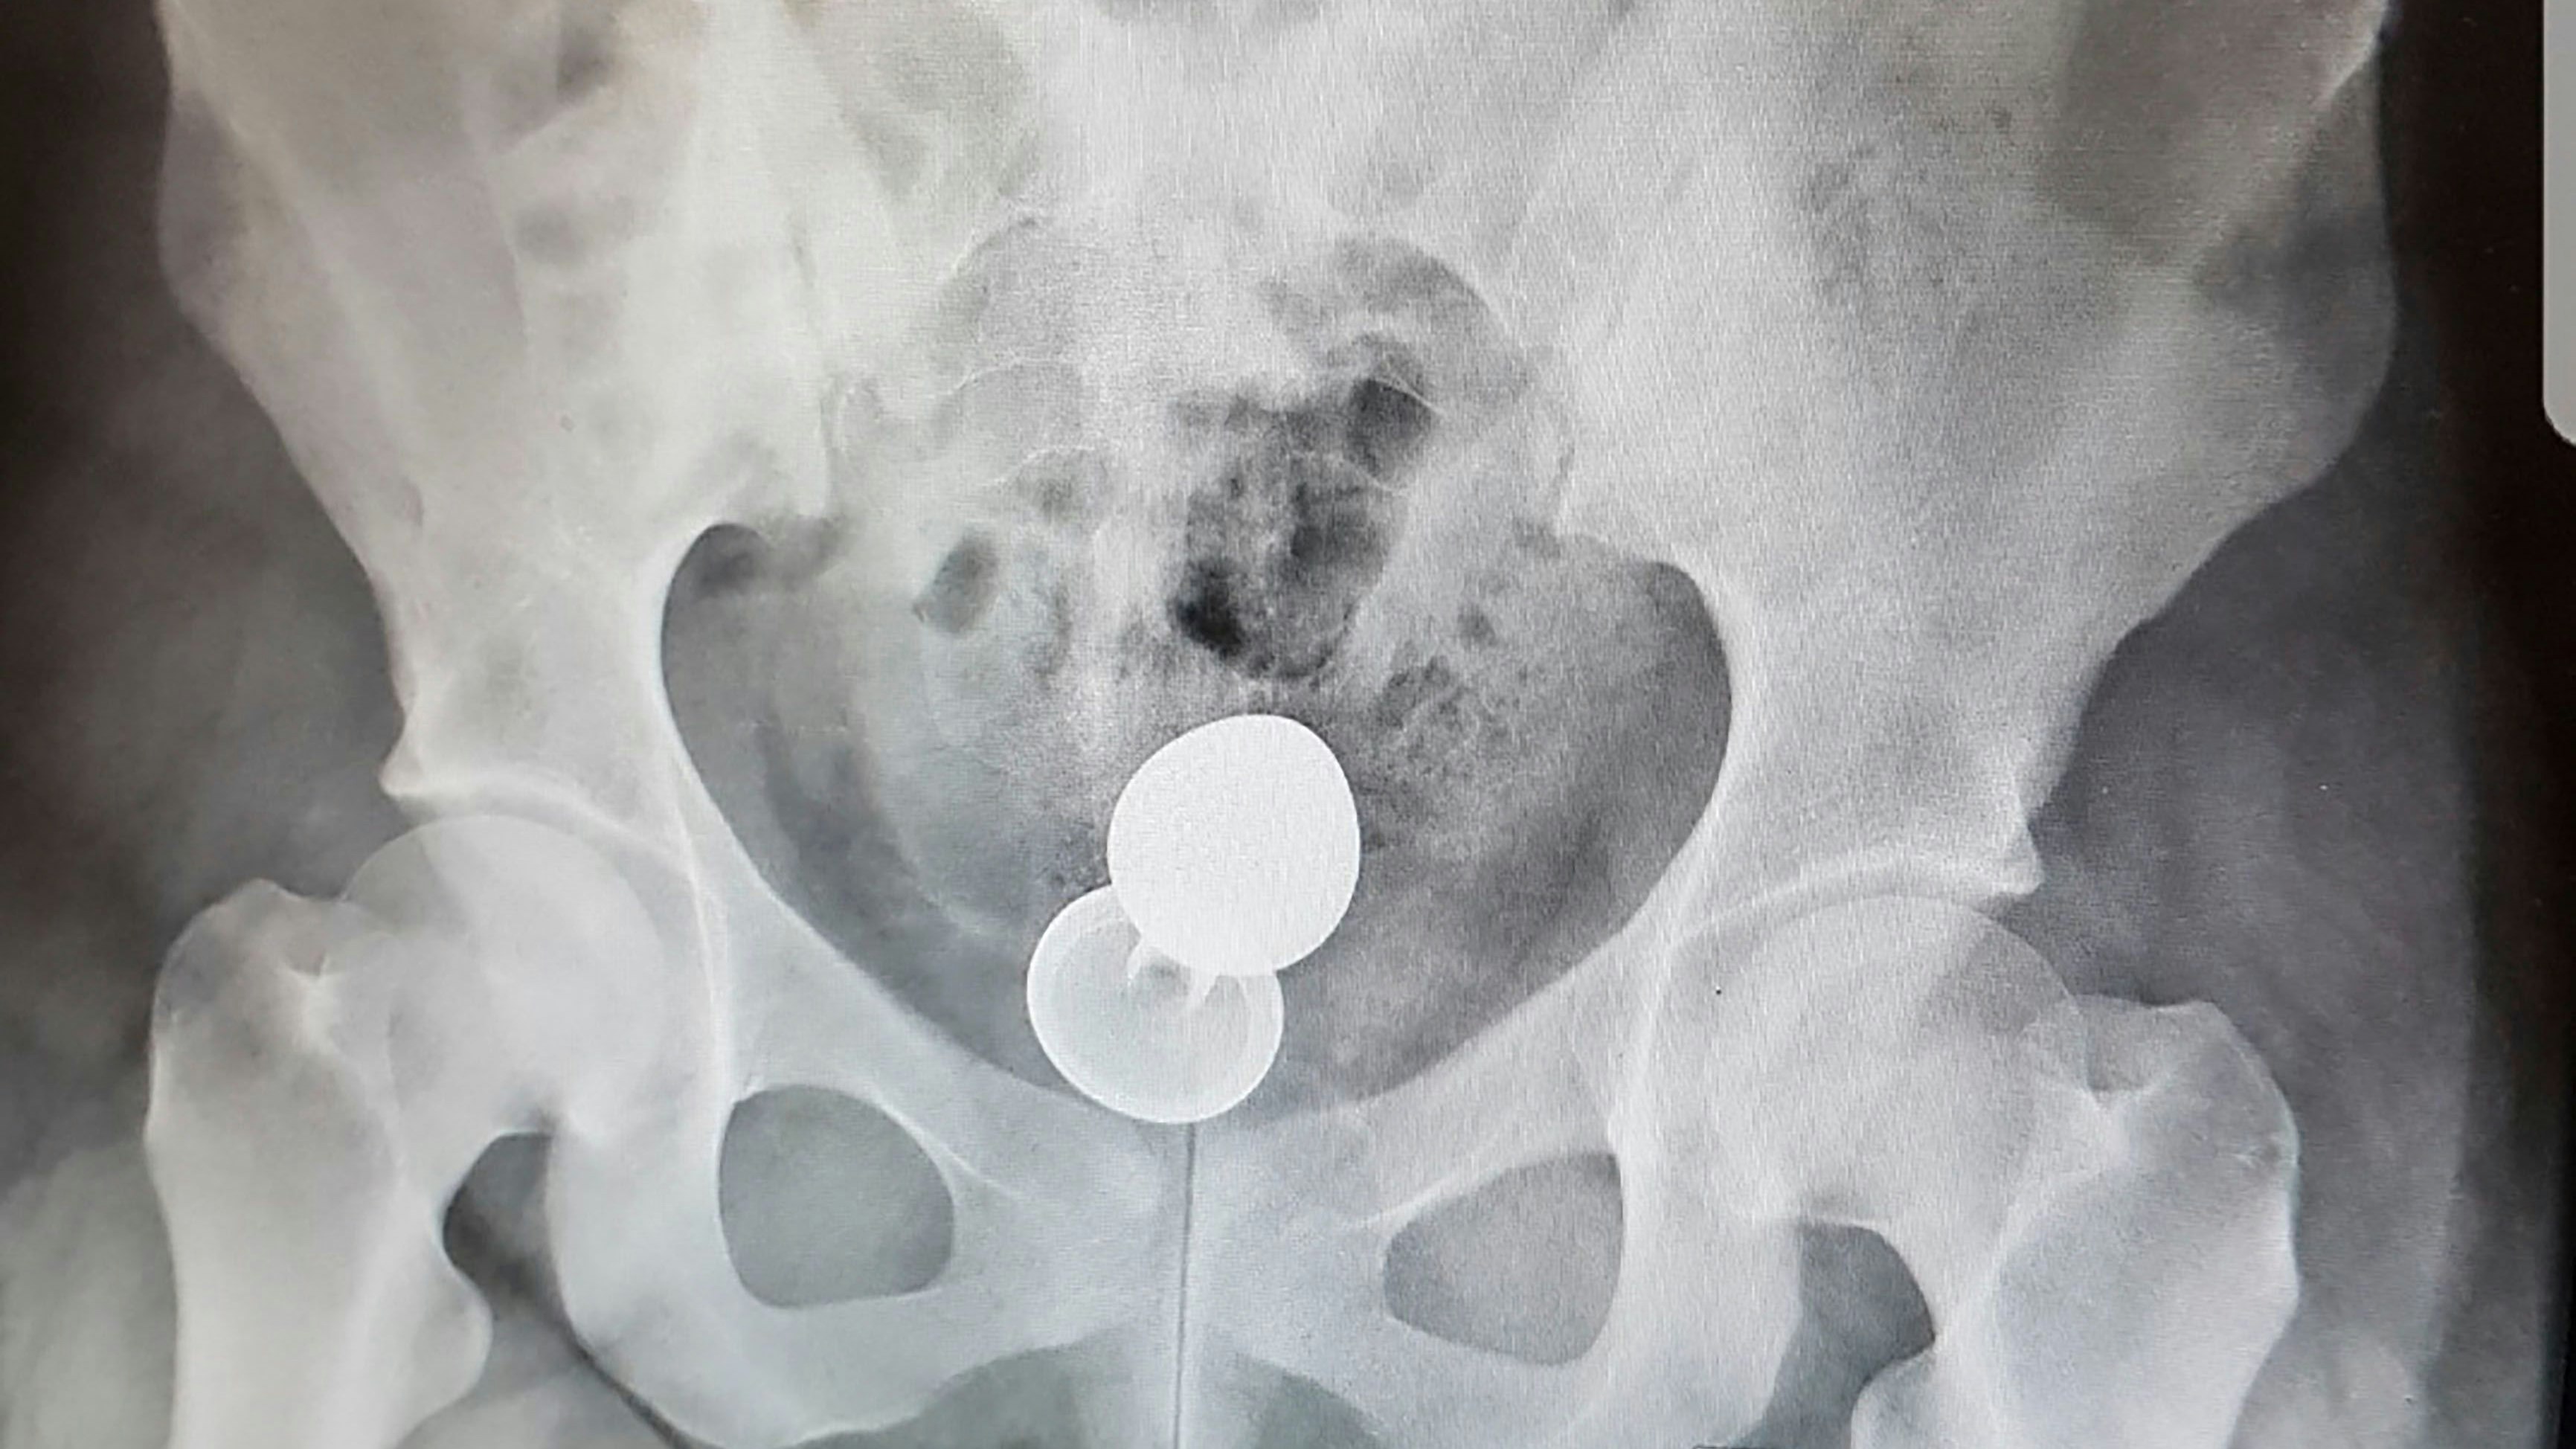

Sexspielzeug blieb in Darm stecken